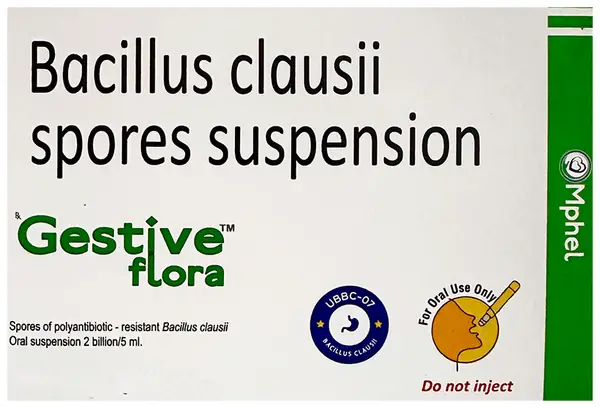

Gestiveflora Oral Suspension (5ml Each)

Mphel Pharmaceutical Pvt Ltd

Composition

Bacillus Clausii2Billion Spores

₹390₹487

Get Substitute at 90% Cheaper

90%

Composition

Bacillus Clausii2Billion Spores

Get Substitute at 90% Cheaper

90%

Gestiveflora Oral Suspension (5ml Each)

Mphel Pharmaceutical Pvt Ltd

₹

390487Rx Required